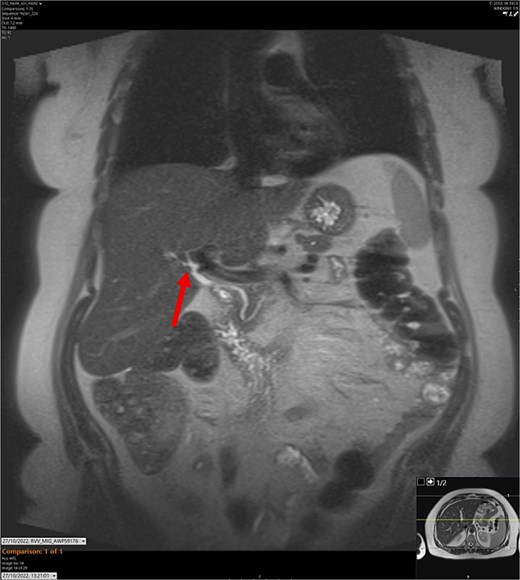

T2-weighted MRCP scan in coronal view. The arrow points to where we expect the gallbladder to be seen, but it cannot be visualized on the scan.